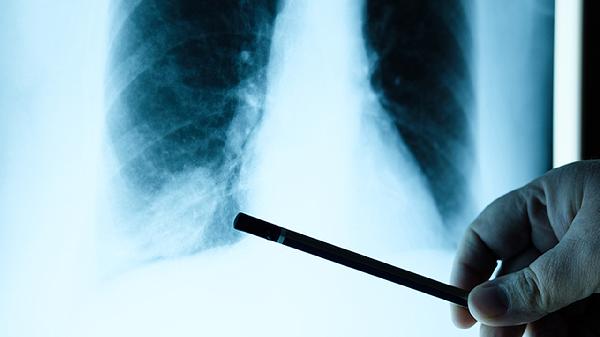

1、定期低剂量CT筛查

40岁以上女性建议每年做一次,有家族史者可提前到35岁。